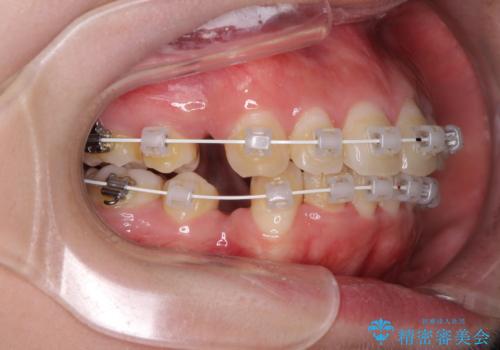

- 矯正装置

- 審美装置

4本の歯を抜歯したことで、飛び出していた口元が引っ込み、横顔が大きく改善されました。

咬み合わせが悪化することのないようにスペースを閉じていくことができ、比較的スムーズに治療を進めることができました。